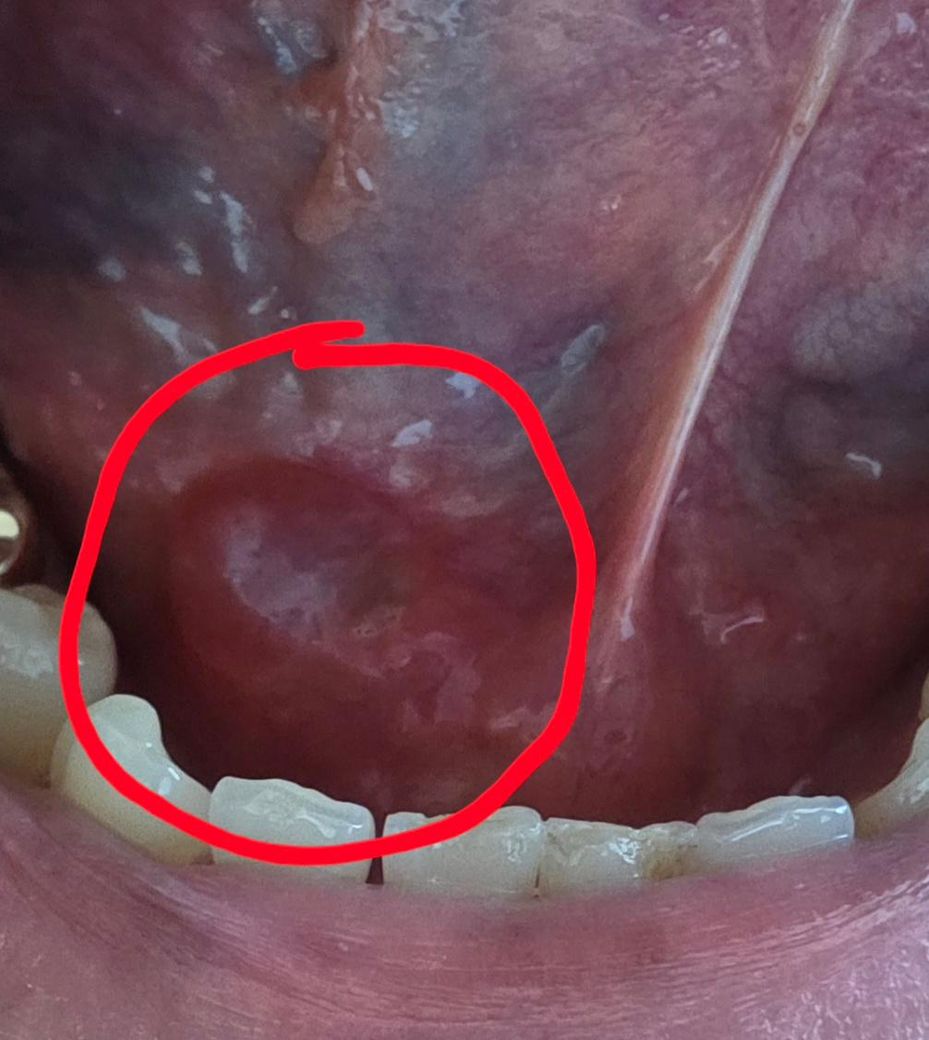

3월 31일에 대학병원에서 혀밑 침샘에 뭔가 있다해서 . 주변 침샘도 같이 긁었다고 들었는데

4월15일 실밥을 제거 했는데 지금 엄지손톱? 크기로 부풀어 올라있습니다. 사진상으로는 잘 안보이겠지만 좀 투명한? 그렇다고 혀로 눌러도 터지지도 않는? 이상합니다

잘못된걸까요? 이런 수술이 처음이라서 좀 무섭네요 ㅠ 일요일이라 병원도 못가요...

하마종,ranula로 추정됩니다 침샘쪽 문제가 맞고요 수술 후 재발한 것 같습니다 응급상황은 아니고요 치과 다시 가보시면 됩니다